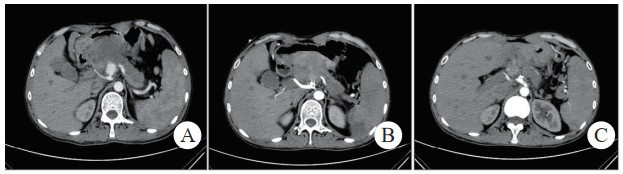

重症急性胰腺炎的早期,由于炎症反应,血管内皮损伤和血管通透性增加,液体转移到腹膜和间质,同时还因呕吐、经口摄入减少、经呼吸道蒸发增加和出汗等导致血管内血容量减少[3-4](仅有血浆的减少,无血细胞的丢失),血液浓缩,RBC、HB、红细胞比容(HCT)升高,体温上升、心率升高、血压下降、呼吸加快等;针对患者早期症状进行病因处理、积极适当体液复苏等;患者通过液体复苏,血容量增加,低血容量症状改善,HB、RBC、红细胞比容(HCT)下降恢复至正常水平,体温、心率、血压、呼吸恢复正常;但患者在治疗过程中由于各种原因出现“腹腔出血”时,大量血液从血管内丢失,血容量减少(全血丢失),尽管通过静脉补液,血容量恢复,血压正常,低血容量症状改善,但由于血细胞及血红蛋白的合成需要一定时间,故患者的RBC、HB、红细胞比容(HCT)降低,致使患者的血液载氧能力下降,从而可能出现一系列的贫血症状(头晕、头痛、呼吸短促、脸色苍白等),患者临床症状未能改善,2024美国胃肠道病学会[5]建议尽快进行CT检查探寻原因;若在患者恢复过程中出现“腹腔出血”,患者血容量大量丢失(全血丢失),血压下降、心率代偿性升高,RBC、HB、HCT(血细胞比容)降低,出现低血容量休克。在重症急性胰腺炎治疗、恢复过程中前后生理指标对比见图 4。

| 图 4 重症急性胰腺炎治疗恢复中有无 |

总之,重症急性胰腺炎导致的胰周动脉破裂出血及假性动脉瘤形成采取介入治疗效果满意、长期随访并发症发生率低,但需术者熟练掌握技术要点并注意操作手法。在患者诊断为重症急性胰腺炎后,应积极进行治疗,阻碍患者病情进一步发展,降低并发症的发生率,同时在重症急性胰腺炎的治疗恢复期间,应密切关注患者的临床表现、生理指标等,对于经治疗后症状无改善患者进行CT检查查明原因,正常患者定期进行影像学检查排除假性动脉瘤等并发症的形成发展,一旦发现假性动脉瘤形成,应在常规治疗的情况下立即进行TAE,降低患者的并发症发生率及病死率,同时术后应积极进行影像学复查,排除介入手术术后并发症,具体诊治过程参考图 4。